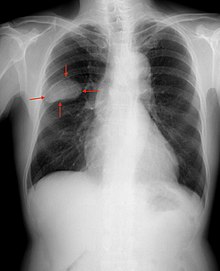

Le cancer du poumon non à petites cellules, ou NSCLC, est le type le plus commun de cancer du poumon. “Métastatique” signifie que le cancer s’est propagé au-delà de son site d’origine, et “non-squameux” signifie que le cancer ne commence pas dans un type de cellule dans les poumons appelé cellules squameuses. La plupart des NSCLC sont non-squameux.